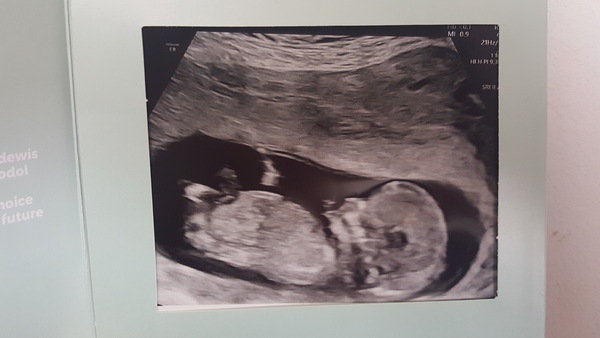

Back from the scan, all looking well thank goodness!!

Great scan pic @bellanotte22 !! Congrats

Thank you HanahMarie they've moved ne forward to the 18th :)